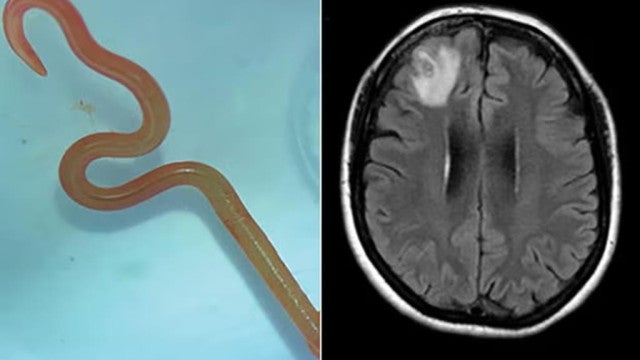

O neurocirurgião, Dr. Hari Priya Bandi, retirou um verme parasita de 8 centímetros de comprimento do cérebro de uma paciente, o que a levou a procurar Senanayake e outros colegas do hospital para obter conselhos sobre o que fazer a seguir.

“Certamente o cirurgião não esperava encontrar um verme em movimento quando iniciou a cirurgia”, afirmou o infectologista Senanayake. “É normal os neurocirurgiões lidarem com infeções no cérebro, isso acontece regularmente. Mas esta foi uma descoberta única na carreira. Ninguém esperava encontrar aquilo”, disse.

“Canberra é um lugar pequeno, então pegámos no verme ainda vivo e mandamos para o laboratório de um especialista da CSIRO (Commonwealth Scientific and Industrial Research Organisation) que tem uma vasta experiência com parasitas”, contou Senanayake. “Ele olhou para a minhoca e reagiu imediatamente: Oh meu deus, é uma ‘Ophidascaris robertsi’.”

Ophidascaris robertsi é um verme geralmente encontrada em cobras pítons e a paciente do hospital de Canberra marca o primeiro caso mundial do parasita encontrado em humanos.